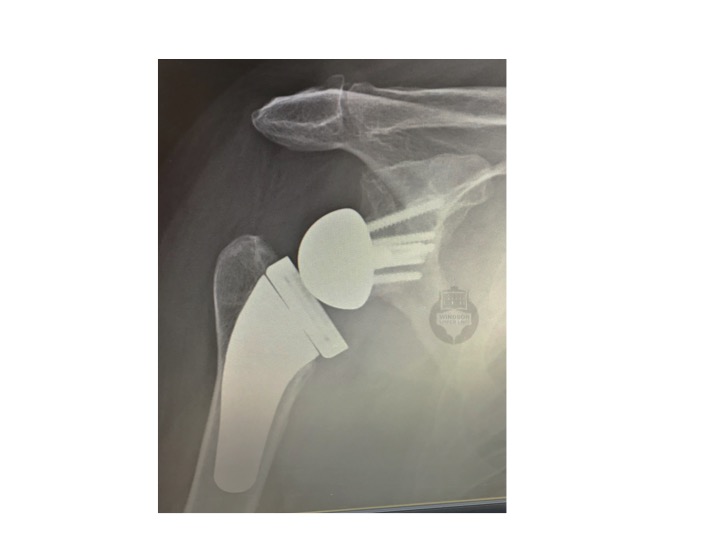

By reversing the ball  and socket this improves the physics in your shoulder if your rotator cuff has failed. It moves the centre of rotation of the shoulder more medially and lower down.  In doing so the lever arm of the deltoid muscle is doubled and the muscle is tensioned - this makes it much more powerful - enough to allow you once again to raise your arm.  Also, the ball which now lies on the shoulder blade blocks upward migration of the humerus, so the fulcrum is maintained in the optimum position to allow the arm to be raised up. The x-ray below shows a reverse geometry total shoulder replacement in a patient who was absolutely delighted with his outcome six months after his surgery.

This operation normally involves a 2-3 day stay after surgery.  It is performed under a general anaesthetic and regional nerve block.  An incision is made over the front of your shoulder and your damaged joint surfaces are removed.  These are replaced by precision engineered metal and plastic implants.  As mentioned above, in a reverse total shoulder, the ball and socket are switched around, so the ball now sits on your shoulder blade and the socket is now on your arm bone.